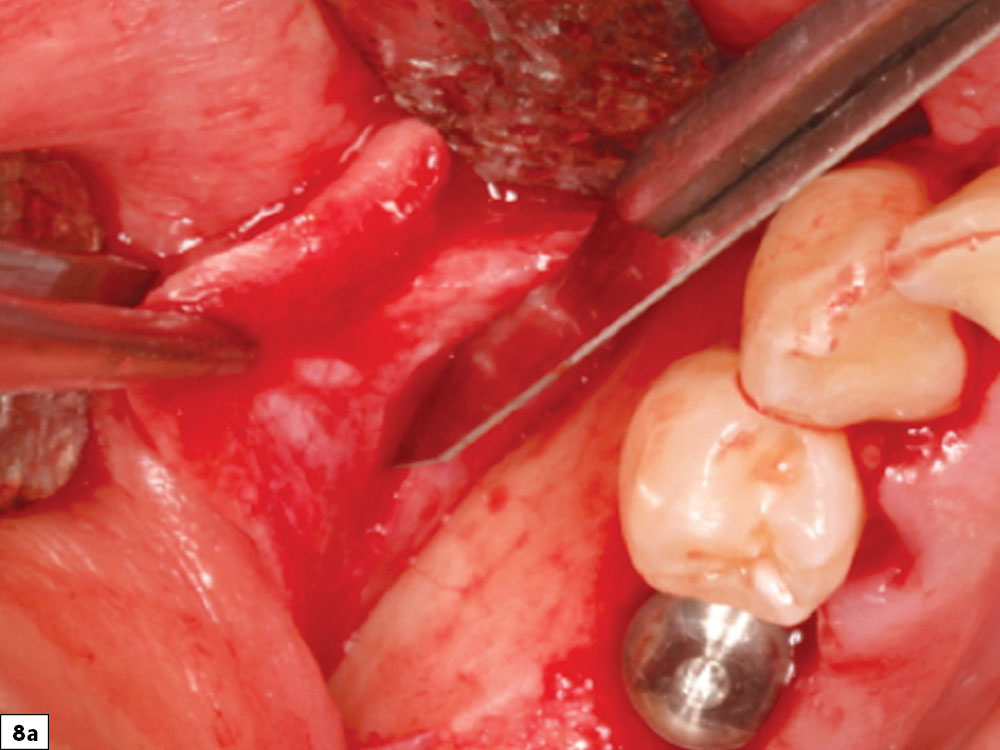

Flap tension is reduced by releasing the periosteal layer, allowing the elastic fibers of the underlying flap to stretch as the flap is drawn over the graft site. Stretching the tissue may be completed by either periosteal release incisions (shallow incisions with a scalpel blade in the periosteum) or a blunt dissection (Metzenbaum scissors placed into the periosteal tissue layer and opened, resulting in stretching of the tissue fibers). Ideally, extension of the flap should extend at least 5 mm beyond the edge of the adjacent margin after the flap is released (Figs. 8a, 8b).

Periosteal release incisions with a No. 15 blade

Broadbased tissue release with Metzenbaum scissors

Figures 8a, 8b: Periosteal release incisions with a No. 15 blade (8a), and broadbased tissue release with Metzenbaum scissors (8b).